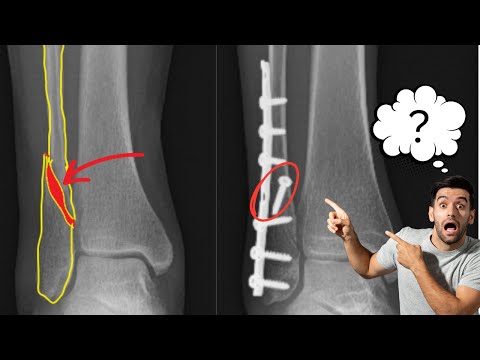

Hellow guys, Welcome to my website, and you are watching Ankle Surgery-Ankle Arthroscopy (Scope) and Lateral Ligament Repair. and this vIdeo is uploaded by Tidewater Orthopaedics at 2019-04-09T07:11:30-07:00. We are pramote this video only for entertainment and educational perpose only. So, I hop you like our website.